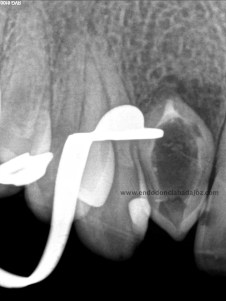

Nuestro caso, se trataba de esta pieza con necrosis pulpar con afectación periapical que presentaba una vía de drenaje (fístula). Esta radiografía muestra el camino de la fístula a la lesión apical.